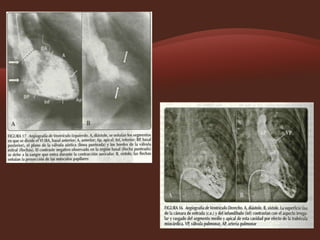

Imágenes angiografías